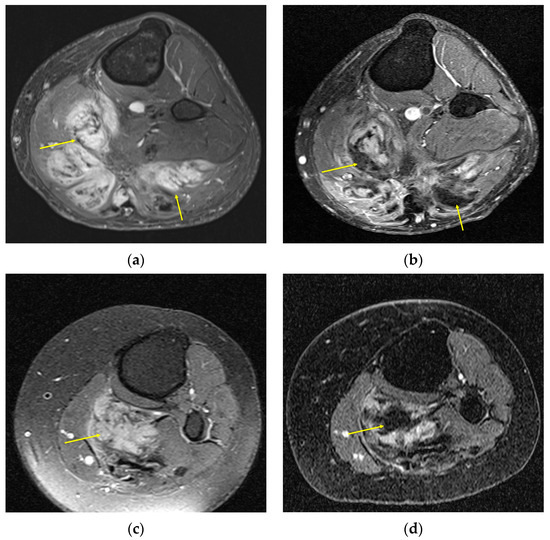

In general, patients that were considered to have a treatment response through RECIST also demonstrated MRI signal changes, although a greater number of patients were considered to have treatment response with MRI signal changes, and the MRI signal changes often preceded the threshold size changes required for RECIST [23,25,29]. However, typical signal changes vary across treatments; for example, systemic therapy often induces collagenization, whereas cryoablation creates tumor necrosis, resulting in different MR appearances (T2 hypointensity versus hyperintensity, respectively), as shown in Figure 4. Tumor enhancement, however, generally decreases in the setting of treatment response, irrespective of treatment modality, and may represent a more attractive imaging endpoint, although there is a lack of consensus around appropriate PR and PD thresholds. Whether one- or two-dimensional measurements or signal ratios of enhancing tumor components are used depends on the response criteria selected, though recently they were all shown to perform poorly when correlated with PFS [30].

Figure 4.

A 36-year-old woman with an abdominal wall desmoid tumor. Pretreatment T2 images (a) were predominantly hypointense suggesting low cellularity. The patient underwent cryoablation therapy shown in axial CT (c) with ablation probe (arrow) and subcutaneous gas (arrowheads). Posttreatment T2 (b) shows heterogeneous increased internal T2 signal (arrow), which could be mistaken for increased cellularity. However, comparison of the preablation (d) and postablation (e) postcontrast T1 images show marked reduction in enhancement with increased internal fluid levels (arrow), compatible with post-ablation necrosis.